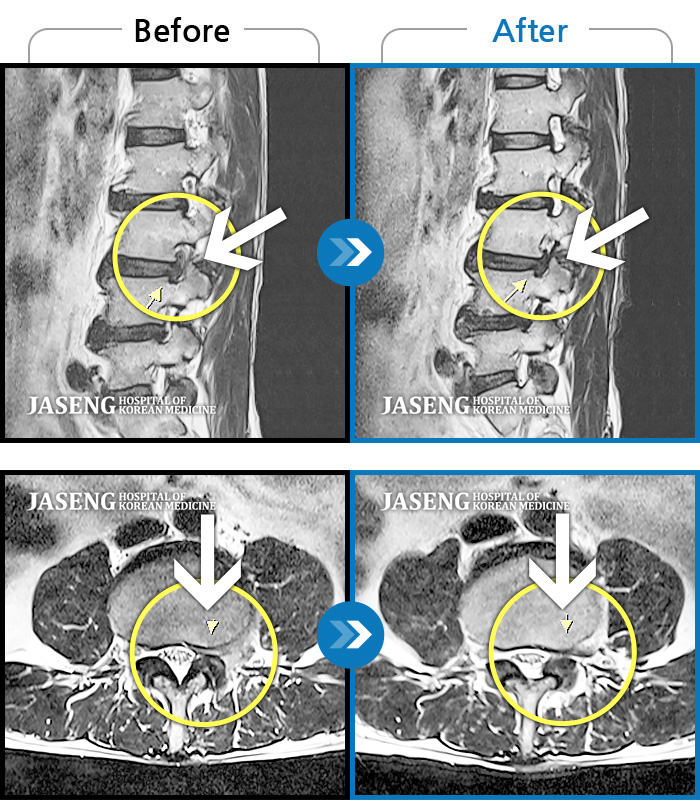

입원하기 전 후의 허리상태는 극과 극으로 너무 좋아져서 행복합니다.